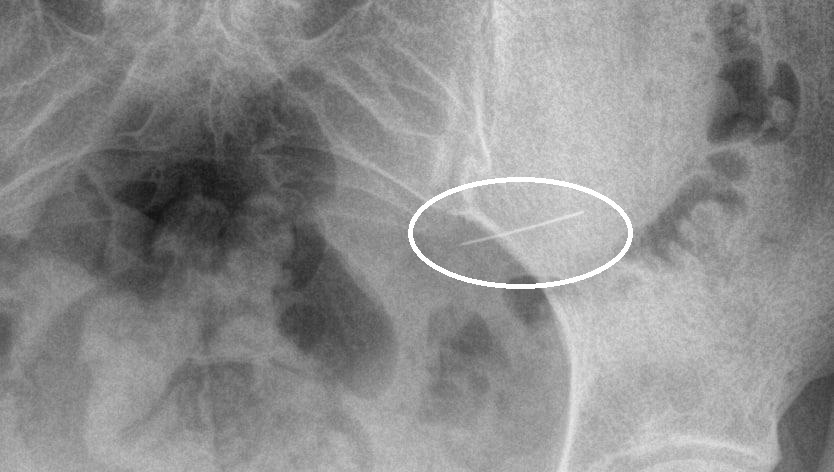

Врачи Красногорска извлекли из желудка девушки швейную иглу

"В Красногорскую больницу поступила девушка, случайно проглотившая швейную иглу. Рентгенологическое исследование показало, что инородное тело находится в желудке", — сказано на сайте министерства.